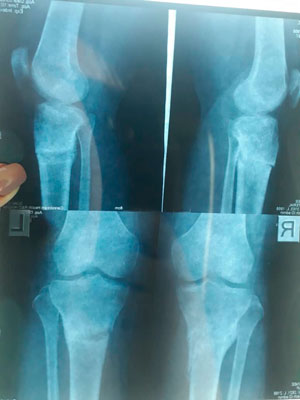

Исходник - 33 года. Киргизия.

Дата операции - 04.03.2019г.

рентген перед снятием аппаратов.